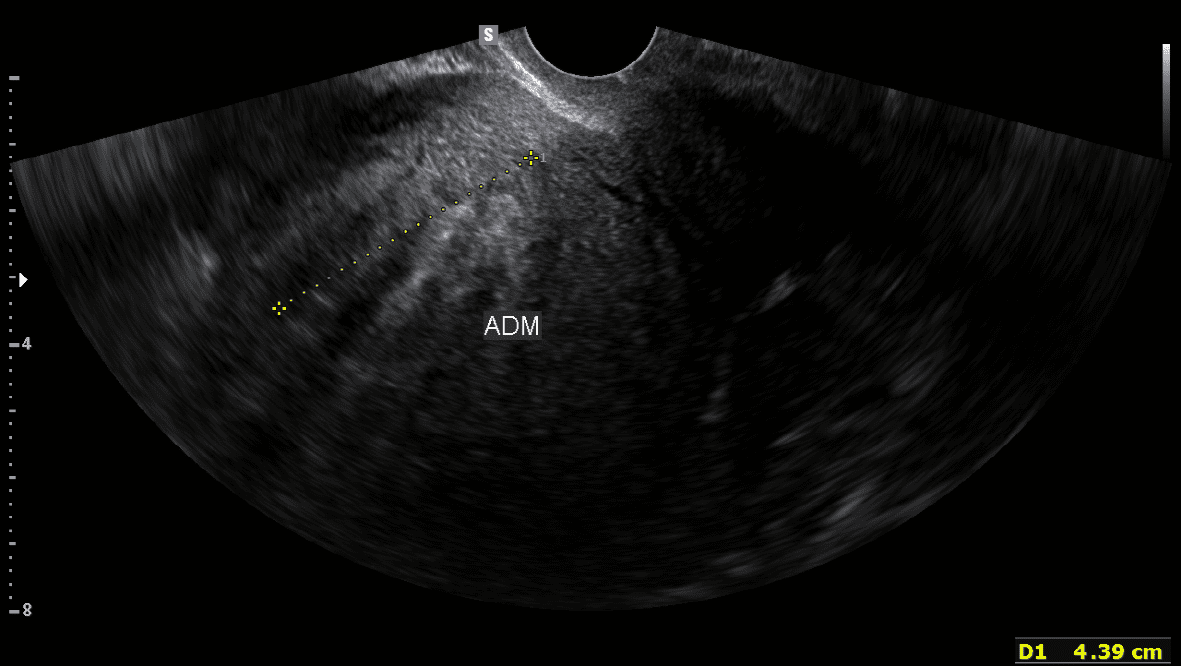

질식초음파로 진단된 자궁근종

질식초음파로 진단된 자궁선종